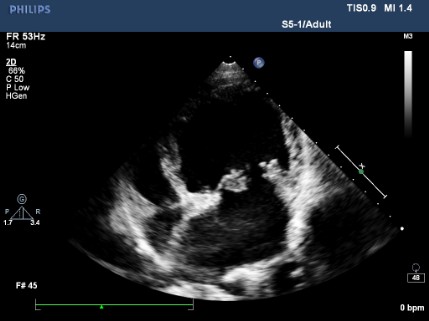

Myxomatózní degenerace mitrální chlopně